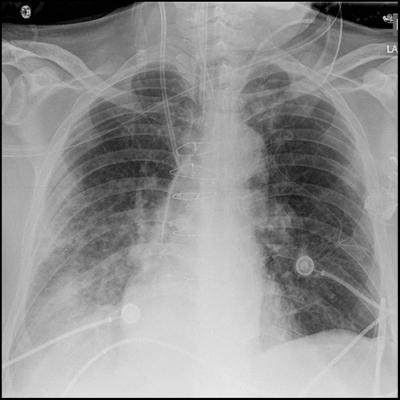

Affecting nearly 200,000 Americans a year, acute respiratory distress syndrome (ARDS) is a sudden failure of the lungs caused by a number of issues ranging from smoke inhalation to pneumonia or blood infection. High-risk patients can develop ARDS after surgery. ARDS is difficult to treat once it develops and is fatal about 30 percent of the time.

Doctors may be able to take measures during surgery to prevent the condition, such as using blood products conservatively, restricting the volume of fluids administered and using different methods to ventilate the lungs. However, only about 3 percent of patients considered at risk actually develop ARDS and testing preventative measures is costly, time-consuming and may be less than ideal for patients not at high risk. Therefore, researchers in this study focused on identifying patients most likely to develop ARDS after surgery.